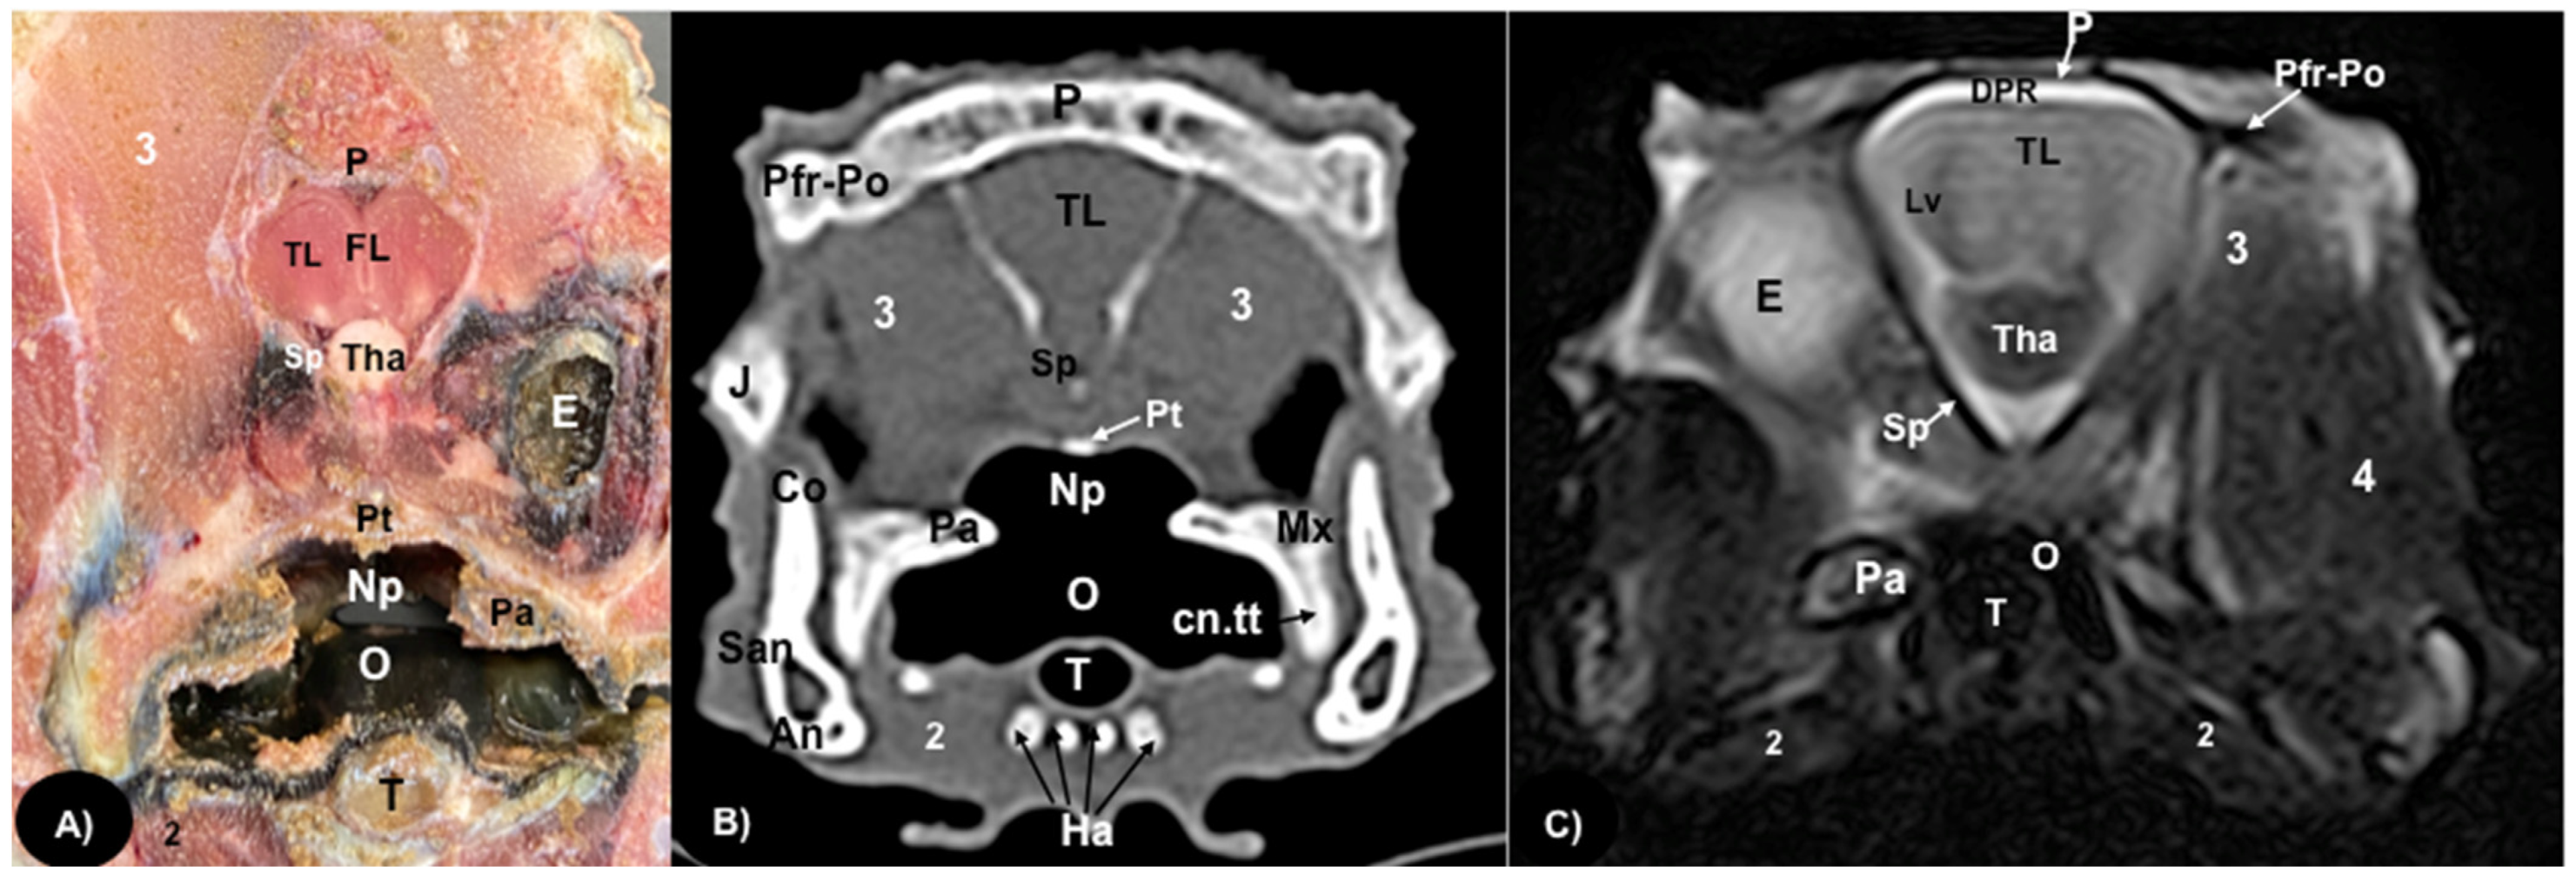

Figure 4.

Transversal gross-section (A), CT bone window (B), and MRI in T2W (C), images of the head of rhinoceros iguana at the level of the frontal bone corresponding to line III in Figure 1. 3: Musculus adductor mandibulae externus medialis. P: Parietal bone. Pfr-Po: Postfrontal-Postorbital bone. TL: Telencephalon. FL: Fissura longitudinalis cerebri. DPR: Dorsal Pallium Rostral Part. Tha: Thalamus. E: Eyeball. Sp: Sphenoid bone. Pt: Pterygoid bone. J: Jugal bone. Pa: Palatine bone. O: Oral cavity. 4: Musculus adductor mandibulae externus Pars superficialis. Mx: Maxillary bone. cn.tt: Caniniform tooth. Np: Nasopharyngeal duct. Co: Coronoid. San: Surangular bone. An: Angular bone. 2: Musculus intermandibularis + Musculus geniohyoideus + Musculus hyoglossus + Musculus pterygoideus + Musculus omohyoideus + Musculus sterohyoideus + Musculus ceratohyoideus. T: Trachea. Ha: Hyoid apparatus.

3.1. Anatomical Sections

3.2. Computed Tomography (CT)

Regarding the neurocranium, the CT images allowed us to distinguish bone structures such as the prefrontal, frontal, postfrontal-postorbital, parietal, squamosal, quadrate, epipterygoid, pterygoid, basioccipital, exoccipital, otoccipital and parabasisphenoid bones (Figure 3B, Figure 4B, Figure 5B and Figure 6B); related to the splanchnocranium, we observed the nasal, premaxilla, maxilla, septomaxilla, vomer, jugal and palatine bones, and the nasal septum (Figure 2B, Figure 3B, Figure 4B, Figure 7B and Figure 8B); the mandible structures such as the dentary, angular, surangular, coronoid and articular bones (Figure 2B, Figure 3B, Figure 4B, Figure 5B and Figure 6B) and the hyoid apparatus (Figure 2B, Figure 3B, Figure 4B, Figure 5B and Figure 6B). CT scanning and post-processing transverse images showed the relation between the different bones that form the head of the rhinoceros iguana, the junction of the nasal and the prefrontal bone, as well as that of the parietal bone with the postfrontal-postorbital bone (Figure 2B and Figure 4B), and the palatine and quadrate processes of pterygoid bone (Figure 5B and Figure 6B respectively). The prominent medial horn was identified dorsal to the nasal bone with soft-tissue attenuation and a thin, lamellar-shaped mineral structure bordering it regularly on its most external aspect (Figure 2B).

Concerning the nasal cavity, the transverse CT image showed the nasal glands as symmetrical bilateral structures, with regular and well-defined margins, located on both sides of the nasal cavity and with soft tissue attenuation (Figure 2B). Moreover, those structures with intraluminal gas content such as the nasal conchal recess (Figure 2B), oral cavity, nasopharyngeal duct, trachea, adductor fossa (Figure 4B) and the otic cavity (Figure 6B) were identified with this technique, appearing with a vacuum effect. In addition, there were areas of soft tissue attenuation medial to the mandible and bilateral to the hyoid apparatus, compatible with the intermandibularis, genihyioideus and hyoglossus muscles (1 in Figure 2B and Figure 3B), the pterygoideus, omohyoideus, sternohyoideus and ceratohyoideus muscles (2 in Figure 4B), the adductor mandibulae externus medialis and superficialis muscles located, respectively, dorsomedially and ventrolaterally to the adductor fossa (3 and 4 in Figure 4B and Figure 5B).

3.3. Magnetic Resonance Imaging (MRI)

In contrast to the CT images, the bone junctions were not distinguishable on MRI, but those bones that formed the neurocranium, such as the frontal, postfrontal-postorbitary, parietal and supraoccipital bones were identified (Figure 3C, Figure 4C, Figure 5C, Figure 6C and Figure 8B). The cranial musculature was found isointense concerning the thalamus in T2W. This technique enabled a better resolution to identify the muscle groups already mentioned (Figure 2C, Figure 3C, Figure 4C and Figure 5C). In the transverse planes of the encephalon, the cerebral cortex was observed slightly more hyperintense than the white matter, which was more hypointense in T2W sequences (Figure 4C). The diencephalic region (Figure 4C, Figure 5C and Figure 8B) was hypointense (T2W) compared to the cerebral cortex (Figure 5C), showing the thalamus and hypothalamus (Figure 8B). The brainstem appeared hypo/isointense in T2W compared to the cerebral cortex, as well as presenting a markedly tortuous horizontal alignment (Figure 8B). Moreover, the caudal colliculus and the fourth ventricle were also displayed in excellent detail. In the rostral aspect of the telencephalon, we distinguished the dorsal pallium rostral part with its lateral and medial portions (Figure 4C). Interestingly, the dorsal MRI image was quite helpful to identify the olfactory bulb located extracranially, which extended rostromedially between the eyeballs (Figure 3C, Figure 7B and Figure 8B).

The use of MRI was valuable for visualizing organs located in the head. Thus, transverse MR images T2W facilitated the accurate identification of the main components of the brain, such as the telencephalon, diencephalon, mesencephalon, metencephalon and myelencephalon. Therefore, we identified specific structures such as the lateral ventricles, the anterior dorsal and posterior dorsal ventricular ridges, the cerebellum, the fourth ventricle, the dorsal pallium and the brain stem with the caudal colliculus. Interestingly, the dorsal MR T2W image showed the olfactory bulb isointense compared to the telencephalon, located in the rostral portion of the encephalon but in an extracranial situation, remaining in the rostromedial aspect of the eyeballs (extracranial structures). In contrast to other articles that excluded the olfactory bulb description, we present the shape, location and intensity of this structure [31]. This extracranial location was already observed in previous studies on the tawny dragon [31]. However, this finding had not been reported in other species of reptiles, such as the rhinoceros iguana. The gross-section images confirmed the presence of these structures and their rostral extension. Interestingly, in other species, such as galliform birds, the olfactory bulbs are separated from the telencephalic hemispheres but located intracranially, protected by the frontal bone [32].